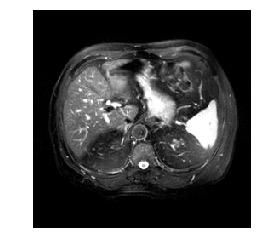

Medical image segmentation methods normally perform poorly when there is a domain shift between training and testing data. Unsupervised Domain Adaptation (UDA) addresses the domain shift problem by training the model using both labeled data from the source domain and unlabeled data from the target domain. Source-Free UDA (SFUDA) was recently proposed for UDA without requiring the source data during the adaptation, due to data privacy or data transmission issues, which normally adapts the pre-trained deep model in the testing stage. However, in real clinical scenarios of medical image segmentation, the trained model is normally frozen in the testing stage. In this paper, we propose Fourier Visual Prompting (FVP) for SFUDA of medical image segmentation. Inspired by prompting learning in natural language processing, FVP steers the frozen pre-trained model to perform well in the target domain by adding a visual prompt to the input target data. In FVP, the visual prompt is parameterized using only a small amount of low-frequency learnable parameters in the input frequency space, and is learned by minimizing the segmentation loss between the predicted segmentation of the prompted target image and reliable pseudo segmentation label of the target image under the frozen model. To our knowledge, FVP is the first work to apply visual prompts to SFUDA for medical image segmentation. The proposed FVP is validated using three public datasets, and experiments demonstrate that FVP yields better segmentation results, compared with various existing methods.